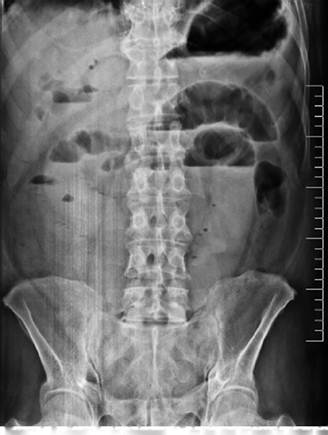

Figura 1. Radiografía de abdomen AP de pie que evidencia datos de obstrucción intestinal alta.

En dicha institución se revalora al paciente, evidenciando al examen físico mal estado general, consciente, orientado, con signos de dificultad respiratoria y desaturación al aire ambiente hasta 70%, saturación hasta 92% con oxígeno por máscara con reservorio a 8 l/min, piel y mucosas moderadamente secas, normocoloreadas, pulmones con murmullo vesicular disminuido con estertores y roncus diseminados en ambos campos pulmonares, abdomen levemente distendido, con ruidos hidroaereos (+) hipoactivos, blando, doloroso a la palpación profunda en mesogastrio, sin datos de irritación peritoneal, tacto rectal con esfínter normotónico, ampolla rectal vacía y dedo de guante explorador limpio, siendo el resto del examen conservado. Se obtienen estudios complementarios de laboratorios en sangre que reportan: leucocitosis de 10 640/ml, con neutrofilia del 88 %, Hb 12 g/ dl (previo de 15,2), normocítica, normocrómica, Hto 34,8 %, hipoproteinemia con hipoalbuminemia severa con proteínas totales de 4,2 g/dl y albumina de 2,1 g/dl, e hipokalemia leve con K de 3,0 mEq/L, además de gasometría arterial que evidenciaba alcalosis metabólica parcialmente compensada con acidosis respiratoria, con insuficiencia respiratoria aguda hipoxémica moderada (PaFiO2 170), y resto de laboratorios del hemograma, coagulograma, glicemia, pruebas renales y hepatograma dentro de parámetros normales. Se obtiene a la vez Rx de tórax PA y abdomen AP de pie, evidenciando en el primero imágenes radiopacas de infiltrado alveolo-intersticial diseminadas en ambos campos pulmonares a predominio del lado izquierdo, y en la segunda, asas de intestino delgado dilatadas con imagen sugestiva de pila de monedas y niveles hidroaéreos a predominio del lado izquierdo (Figura 1). Tras la obtención de estos exámenes y en el contexto del paciente se han tomado en cuenta los diagnósticos diferenciales de obstrucción intestinal vs hemorragia digestiva alta, este último según la institución inicial que realizó la referencia, que indicaba la presencia de vómitos porráceos y el evidente descenso de la Hb en 3 puntos, por lo que se continúa con la indicación de endoscopia digestiva alta la cual reporta: “Datos de obstrucción intestinal alta (debito de retención proveniente de segunda y tercera porción duodenal) (Figura 2), sospecha de metaplasia columnar de esófago, gastritis crónica superficial de antro, estudio parcialmente satisfactorio (por segmentos con debito retentivo no valorables)”. Con estos hallazgos se refuerza mucho más la primera hipótesis, pero llama la atención que un paciente sin antecedentes quirúrgicos abdominales presente datos de obstrucción intestinal, además de tratarse de un paciente con un cuadro clínico atípico, y que al momento no había podido ser resuelto bajo medidas conservadoras, por lo que se decide solicitar estudios ampliados extrainstitucionales, como una tomografía axial computarizada (TAC) de abdomen con contraste de forma urgente; tras gestionar la misma, se obtiene reporte que indica (Figuras 3y4): “Hallazgos tomográficos compatibles con íleo biliar (imagen de cálculo de 4 x 3,2 cm con áreas de calcificación en su pared a nivel de yeyuno proximal), probable fístula bilio-digestiva (colecistoduodenal), neumobilia, pequeños quistes renales simples bilaterales, hallazgos de la porción valorable de tórax sugerente de proceso infeccioso de etiología viral sugestivas de COVID-19”. Con ello se solicita la valoración por el servicio de cirugía que, en misma fecha de ingreso, realiza procedimiento quirúrgico de laparotomía exploradora, enterotomía, extracción de cálculo y enterorrafia, con diagnóstico postoperatorio de “Obstrucción intestinal alta, íleo biliar, neumonía por SARS-COV2, hiperplasia prostática”, describiendo en los hallazgos operatorios un cálculo de aproximadamente 4 x 4 cm que ocupaba la totalidad de la luz yeyunal a +/- 60 cm del ángulo de Treitz.

En relación a los hallazgos imagenológicos, la imagen en pila de monedas sigue teniendo alto valor diagnóstico en patologías obstructivas del intestino delgado como es en el caso nuestro, al igual que menciona Carpio-Deheza G5 en su publicación de abdomen agudo quirúrgico. En mención a imagenología se recomienda una adecuada valoración de los estudios iniciales que en sospecha de íleo biliar podrían ayudar al diagnóstico y evidenciar la conocida Triada de Rigler, que hace mención de la conjunción en la radiografía de abdomen de pie de: neumobilia, asas de intestino delgado dilatadas y la visualización directa o indirecta de un cálculo en intestino delgado, y en ocasiones, el cambio de posición del lito en radiografías de control. En la revaloración del caso de nuestro paciente se evidencia dos de estos signos específicos, asas de intestinos delgado dilatadas y una tenue imagen sugerente de neumobilia, siendo el hallazgo de dos de los signos de la triada de Rigler patognomónicos de íleo biliar según Aguila-Gomez MV; es así, que el uso de ésta puede ayudar y prescindir de elementos no coste-accesibles en algunos casos8.